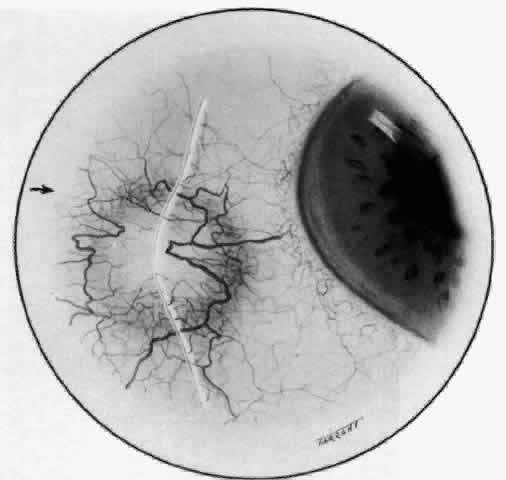

The characteristic features of necrotizing scleritis on fluorescein angiography are hypoperfusion and, eventually, nonperfusion of the vascular networks (Figs. 40 through 43).26 The initial changes are on the venous side of the capillary network; the transit time of the dye increases even if the eye is red and congested. If the disease process persists or has been present for a long time, thrombosis and permanent vaso-occlusive changes occur. These vessels (or the occluded capillary network) are bypassed by the opening of anastomotic channels. New vessels in a granuloma give rise to deep intrascleral leakage of dye (see Fig. 43). Conjunctival and episcleral involvement by the destructive change is late but is always preceded by vaso-occlusive changes that can sometimes be detected with use of the red-free light on the slit lamp (Figs. 44 and 45).

Fig. 40. Early necrotizing scleritis. There is characteristic yellow discoloration of the sclera underlying the conjunctiva at a point of necrosis. In this instance a small filament of tissue has penetrated the conjunctiva.

Fig. 41. Late stage of fluorescein angiogram adjacent to the site of necrosis in the same patient as in Figure 40. Although the eye is uniformly congested, the area near the necrosis shows vascular shutdown, whereas the rest of the conjunctiva and episclera is normally perfused.

Fig. 42. Late arterial phase of fluorescein angiogram in a patient with necrotizing scleritis. All the vessels except the main trunk and the vessels around the limbal perforating vessels are occluded and remain unperfused throughout the angiogram.

Fig. 43. Late venous phase of angiogram of a patient with necrotizing scleritis showing late deep leakage from vessels on the surface of the sclera and leakage of the capillary network at the limbus and the vessels draining it, together with poor or absent perfusion of the remaining vessels.

Fig. 44. Necrotizing scleritis. An avascular patch is seen in red-free light. If left untreated, this will progress to the situation found in Figure 45.

Fig. 45. Necrotizing scleritis. An area of necrosis is evident in the eye of this patient with localized Wegener's granulomatosis. The conjunctiva adjacent to the white necrotic tissue becomes adherent to the underlying episclera.